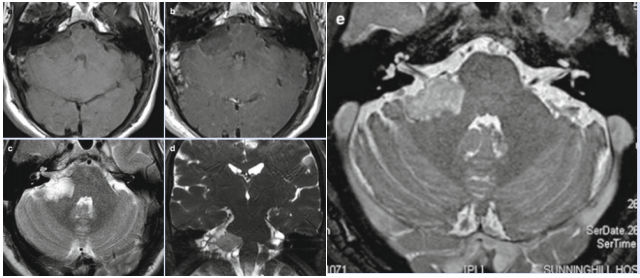

雖然沒有其他的神經(jīng)癥狀,但是醫(yī)生還是建議進(jìn)一步頭部核磁檢查。發(fā)現(xiàn)右側(cè)橋小腦角區(qū)囊實(shí)性占位,罪魁禍?zhǔn)滓伤颇懼?!MRI顯示中等大小的表皮樣突起嵌在腦干和小腦(橋小腦裂)之間的橋小腦角區(qū)內(nèi)側(cè)。而且看起來與七和八腦神經(jīng)的較內(nèi)側(cè)部分緊挨著,特別是它們的進(jìn)出區(qū)。在T1和t2加權(quán)像上,病灶與腦脊液等強(qiáng)度(a,c,d)。未顯示造影劑攝取。膽脂瘤及其與顱神經(jīng)的關(guān)系在CISS圖像中清晰可見(e)。

圖示:MRI顯示右側(cè)橋小腦腳區(qū)膽脂瘤(a-e)